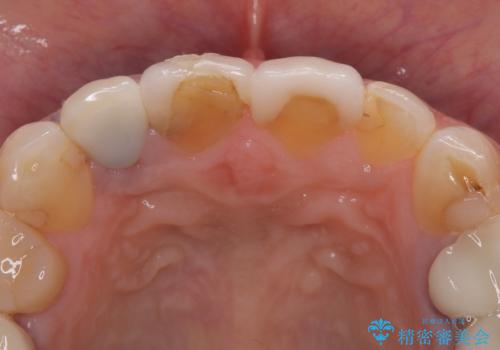

患者様は過去に装着されたラミネートベニアが割れてしまったことに加え、土台との間に隙間が生じており、適合が不良な状態でした。

このままでは見た目だけでなく、むし歯や歯周病のリスクが高まってしまいます。

そのため当院では、上顎左右中切歯を適合精度の高いオールセラミッククラウンにて再補綴する治療をご提案し、実施いたしました。